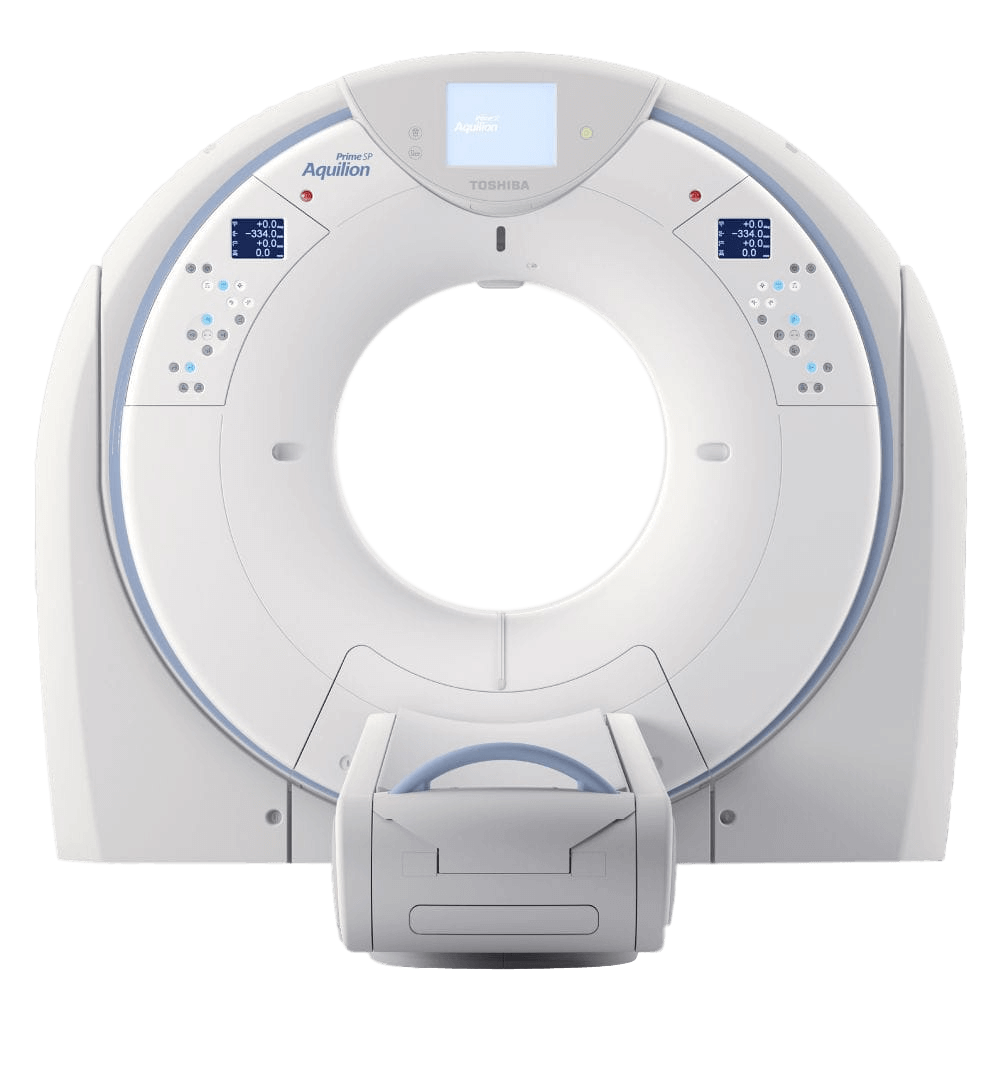

Aquilion Prime SP - это компьютерный томограф, отвечающий всем потребностям врача в области визуализации. Aquilion Prime SP создан на основе передовых технологий, перенесенных с высокотехнологичной КТ, позволяет вам проводить обследования пациентов всех возрастов и с любой массой тела.

Компьютерный рентген сканер Aquilion Prime SP имеет увеличенную апертуру гентри 78 см. Грузоподъемность стола – 220 кг. При необходимости сканирования бариатрических пациентов можно увеличить это показатель до 300 кг. С помощью томографа Aquilion Prime SP можно легко внедрить современные технологии и методы в рутинные сканирования. Контроль экспозиции и итеративная реконструкция с алгоритмом AIDR 3D Enhanced позволяют получить четкие изображения отличного качества при правильном уровне лучевой нагрузки.

Aquilion Prime SP - это правильный выбор для любого диагностического отделения. Aquilion Prime SP обеспечивает высокую производительность, безопасность для пациентов, а также платформу для расширения портфеля изображений для повышения производительности.

Основные характеристики системы:

- Покрытие по оси Z до 4 см;

- 0,5 мм × 80 ряд детекторов PUREViSION4;

- Вращение 0,35 сек;

- Портальный канал 78 см;

- Расширенное поле для исследования - 70 см

Aquilion Prime SP - это правильный выбор для любого диагностического отделения. Aquilion Prime SP обеспечивает высокую производительность, безопасность для пациентов, а также платформу для расширения портфеля изображений для повышения производительности.